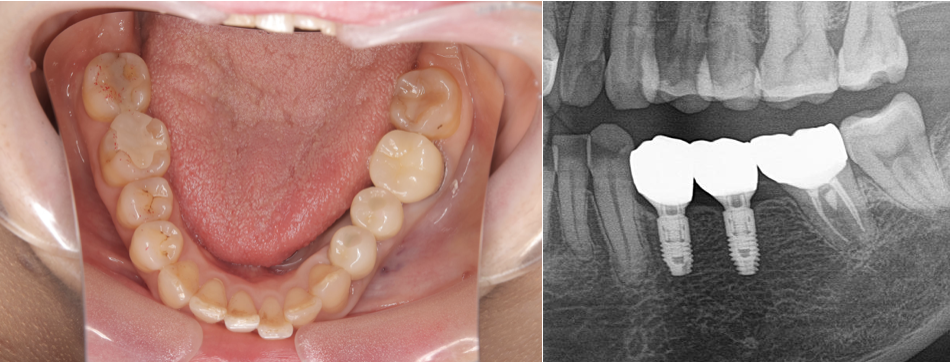

インプラント治療後の写真とレントゲン写真

インプラント治療により、自然な見た目で、ご自身で取り外す必要がなく快適に過ごすことができるようになったと考える。また、インプラント治療により人工歯根が噛む力を支える柱となり、その他の歯に過剰な負担がかかるリスクを軽減できたと考える。

内容:下顎左側第一小臼歯、第二小臼歯に対するインプラント治療